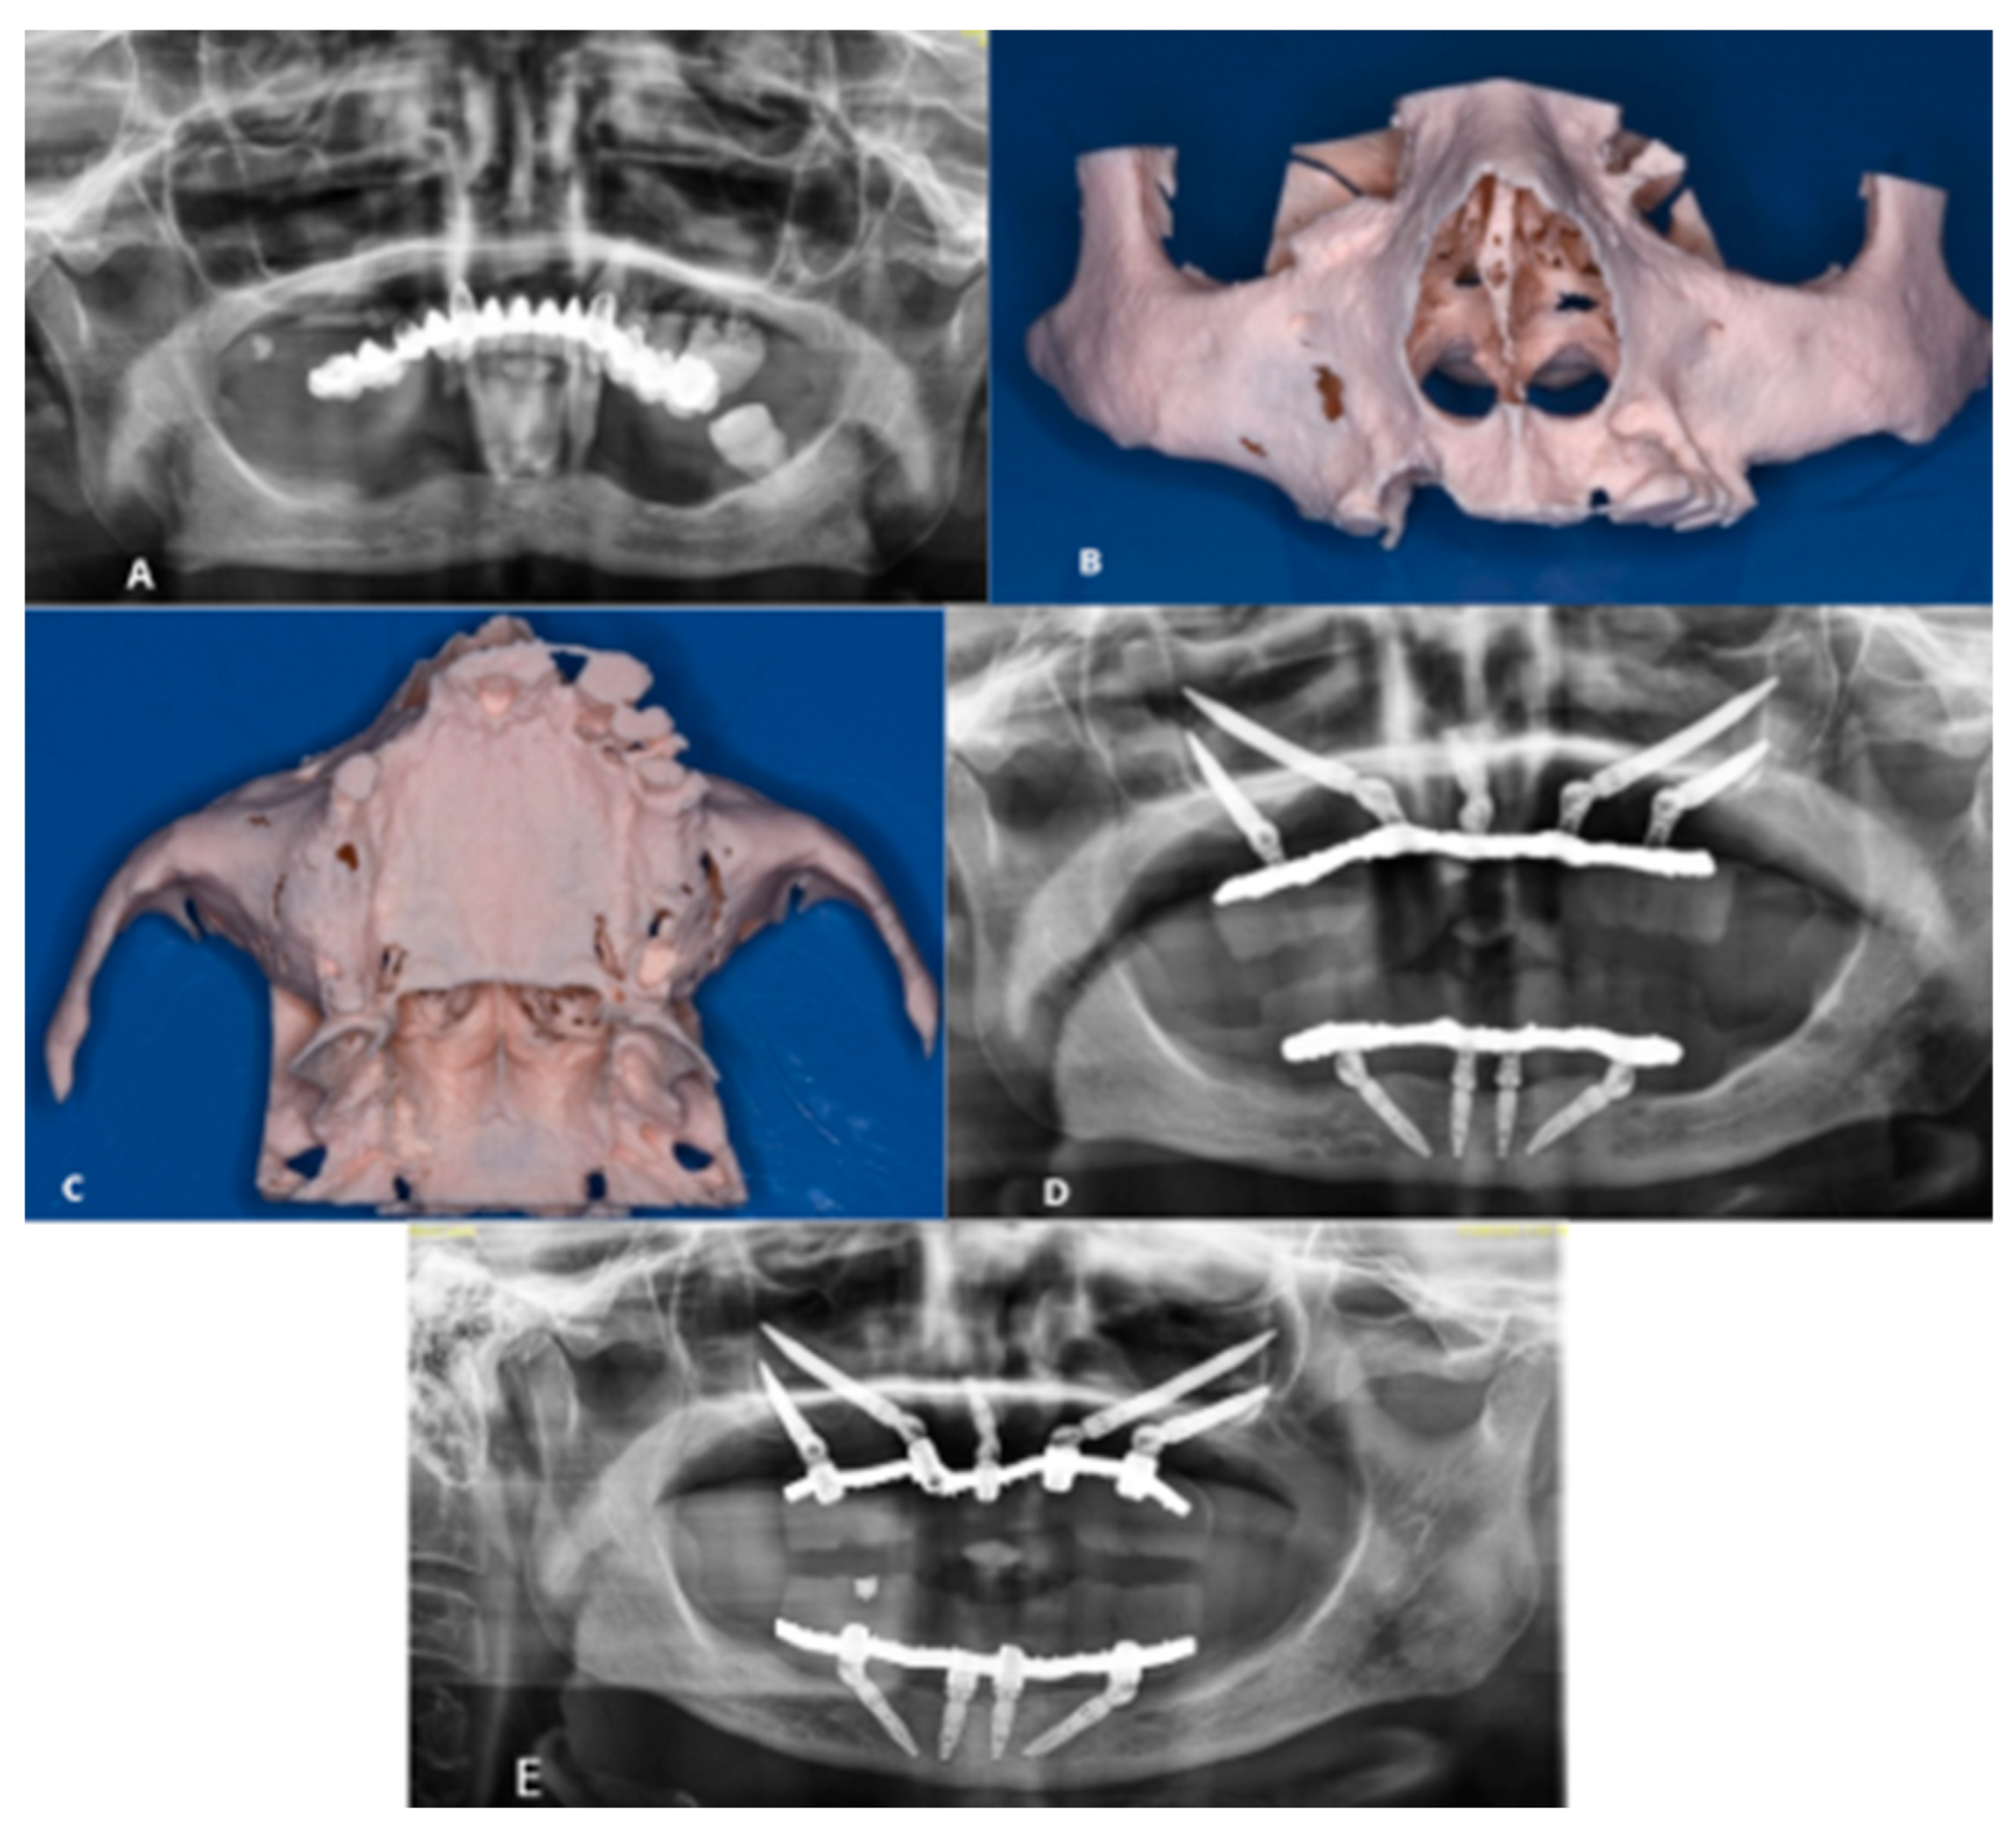

2.3. Case 1